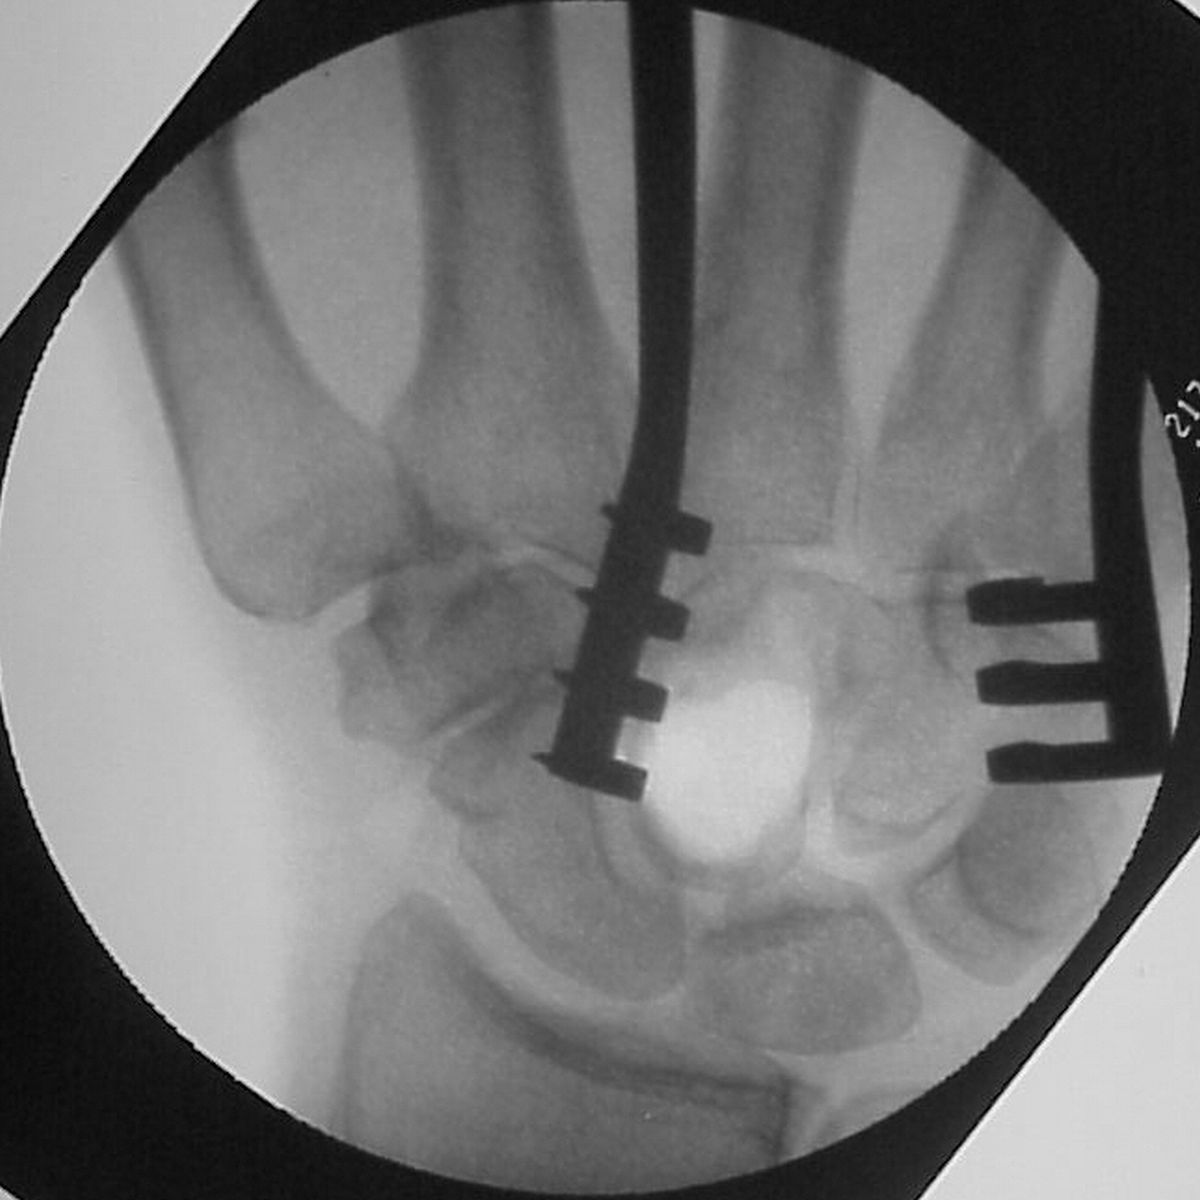

| and then after the

defect was filled with corticocancellous iliac crest

bone graft to improve structural stability: |

| Pressure fit bone

graft in place. |